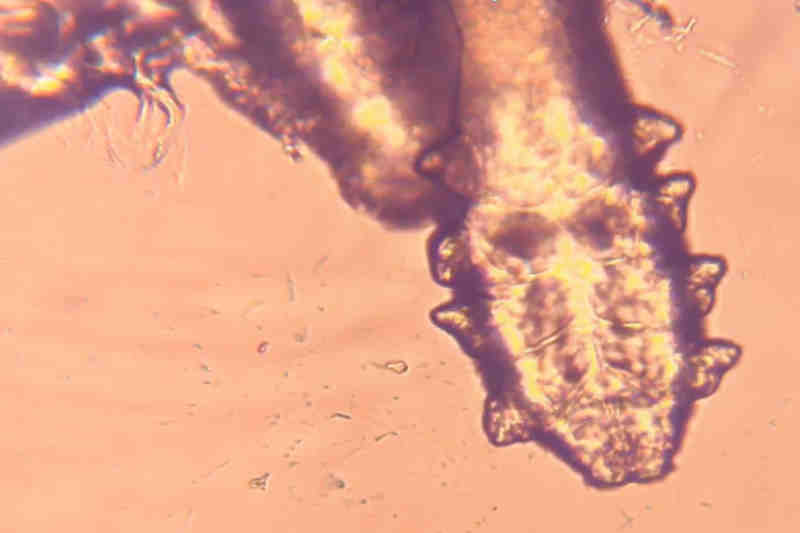

Fig 2. An Eyelid before and after in office treatment with microblepharoexfoliation